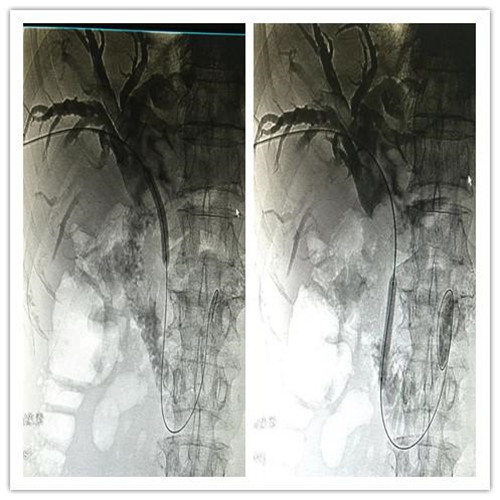

4月4日,乐鱼在线登录入口介入科成功为一位78岁高龄,胆系高位梗阻性黄疸、胆管占位病变的患者紧急成功实施了PTCD(经皮肝穿胆管引流术)。

患者全身皮肤金黄瘙痒难忍,在B超定位下行肝内胆管引流术、术后因引流不畅拔管;在胃镜下逆行ERCP胆管支架植入术,经过术者反复操作,但导丝无法通过病变段。看到患者痛苦不堪,家属迫切治疗的场面,介入科李建国主任现场会诊提出为患者在介入下行PTCD治疗的意见。术前经过讨论制定多套严密方案,与患者及家属多方沟通达成介入手术共识;术中精准定位穿刺选择不同的导丝、导管多角度旋转闭塞原地不动,时间一分一分过去......在医护人员努力下,闭塞的胆道开通了,再经球囊分段扩张病变狭窄段,内外引流管放置顺利300余毫升的黑褐色胆汁流出......

在护理人员精心的配合下,手术历时30余分钟圆满成功,彻底解决了患者梗阻性黄疸引发的皮肤黄染,保护了肝功能。

顺行开通高位胆管梗阻性黄胆经皮肝穿胆管引流术优势明显